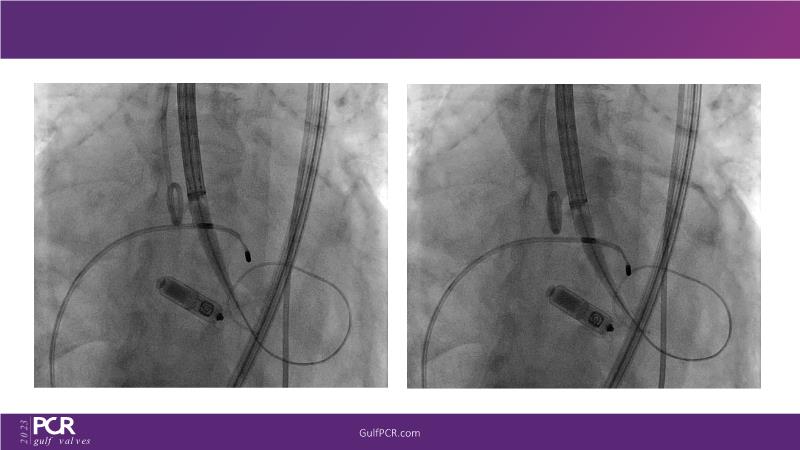

The primary focus of this GulfPCR-GIM 2023 session revolves around pre-procedural planning considerations, valve selection, and managing complex anatomies using both traditional self-expanding valves and the Evolut FX system. Additionally, the session aims to explore the work-up protocol for patients grappling with severe AS and advanced CKD, elucidate the algorithm for selecting the appropriate TAVR platform, discuss strategies to reduce contrast utilization, and highlight the distinctive advantages offered by the Evolut FX system.

• To discuss valve choice in challenging anatomies

• To learn more about optimization of valve deployment